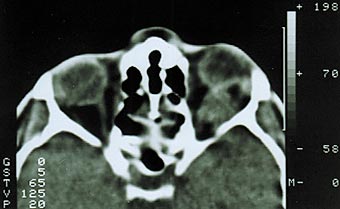

Рис. 2. Компьютерная томограмма той же больной. Видна тень увеличенного зрительного нерва. Менингиома второго типа роста диагностирована у 59% наших больных. Характеризуется прорастанием твердой мозговой оболочки и инфильтрацией экстраокулярных мышц, мягких тканей орбиты [1,6]. Как правило, в начале своего роста опухоль имеет эксцентричное расположение, смещая ствол зрительного нерва (рис. 3). В подобных случаях чрезвычайно трудно дифференцировать эксцентрично растущую менингиому от параневрально расположенной опухоли другого генеза, особенно при отсутствии изменений зрительных функций. Большая часть больных рано предъявляют жалобы на боли в орбите и одноименной половине головы. На глазном дне диагностируют застойный диск зрительного нерва. При длительном анамнезе (до нескольких лет) у трети больных на фоне застойного диска возникают кровоизлияния, развиваются оптико–цилиарные шунты для компенсации вызванного опухолью резкого затруднения оттока венозной крови на уровне решетчатой пластинки [10,11,19]. Зрительные функции сохраняются на высоком уровне несколько лет. Экзофтальм выражен в большей степени и достигает 8–14 мм, может быть осевым или со смещением, сочетается с невоспалительным отеком периорбитальных тканей и красным хемозом (рис. 4). Ограничение подвижности глаза следует расценивать, как симптом прорастания опухолью одной или нескольких экстраокулярных мышц. Чем ближе к вершине орбиты начинается рост опухоли, тем раньше появляется ограничение функций экстраокулярных мышц. Характерным для менингиомы зрительного нерва является отсутствие гиперостоза костей, столь свойственное внутричерепным менингиомам.